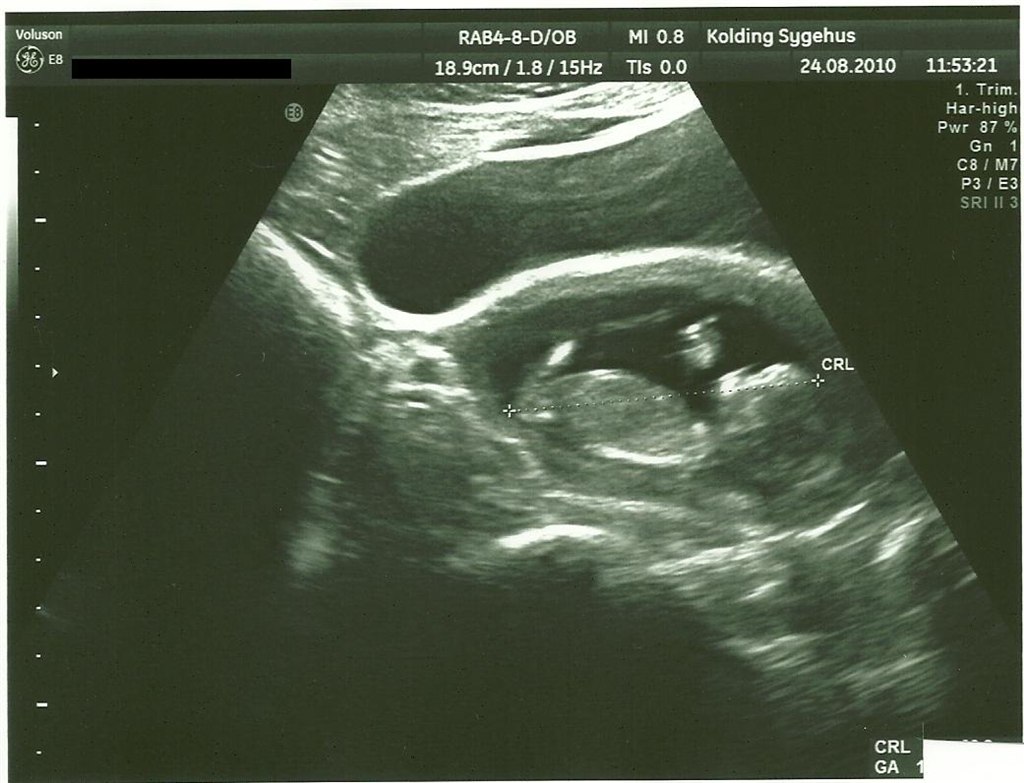

billede 3 - 12+5 nakkefold